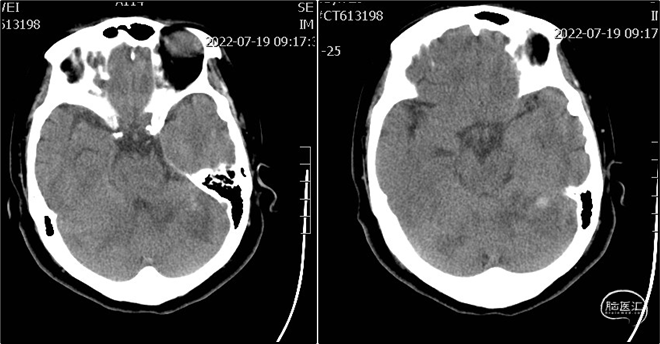

术后第一天复查头颅CT。

术后1月患者NIHSS 2分,mRS 1级;头颅MRI示脑干、双侧小脑、右侧枕叶多发陈旧梗死;CTA示基底动脉近端管腔支架植入术后,未见明显狭窄。